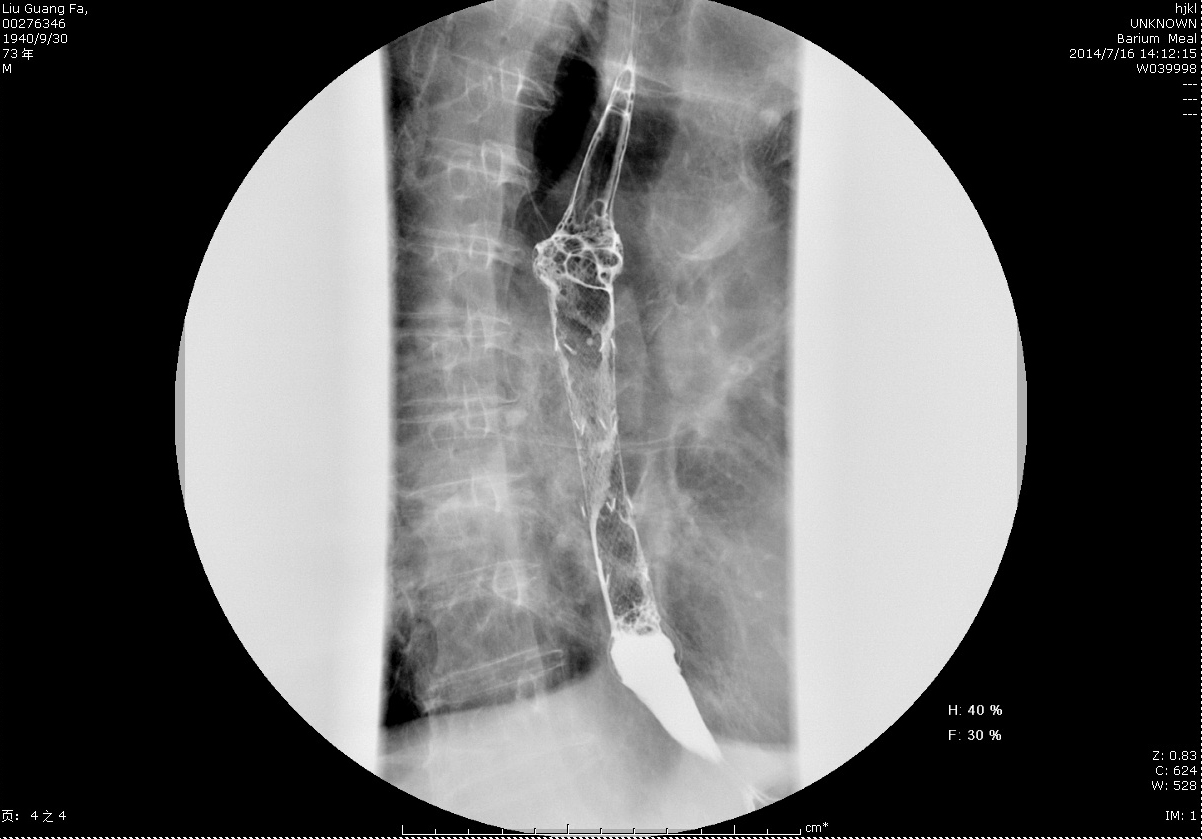

圖4+術(shù)后鋇餐